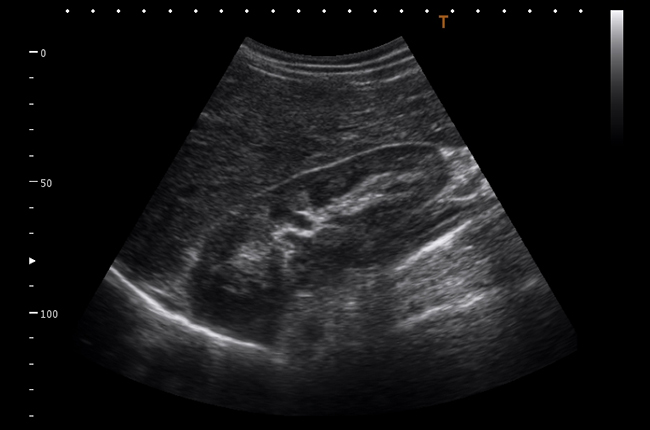

Якщо Вам потрібна висока якість діагностики завжди і всюди, Viamo c100 — це ідеальне рішення. Система Viamo c100 поєднує в собі всі переваги переносної ультразвукової системи та діагностичну точність, ефективність і зручність, які притаманні стаціонарним апаратам.

Viamo c100 – сканер, розроблений для ситуацій, де мобільність – необхідний чинник, а якість зображення має вирішальне значення. Апарат належить до експертного класу та підтримує технології візуалізації останнього покоління, що дозволяє отримати зображення неперевершеної якості – основний чинник успішної діагностики в ургентних ситуаціях.

Акушерство та гінекологія